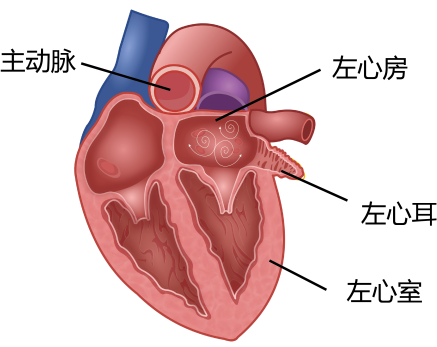

首先在患者的右侧股静脉植入11Fr及8Fr的两个鞘管,分别送入ICE导管及房间隔穿刺系统至右心房。通过对ICE的调控,选择了房间隔穿刺的最佳部位(偏下偏后)。房间隔穿刺成功后,ICE导管可以沿着导丝从右心房进入左心房的左上肺静脉。调整ICE导管后,可以从心腔内对左心耳进行测量,测量显示心耳开口24.1mm,DSA肝位造影测量心耳开口27.98mm,可用深度20.89mm,且心耳内梳状肌发达,属于典型敞口菜花型左心耳,深度极浅,手术难度颇大。考虑到心耳的形态以及稳定性,选择33mm封堵器(图4)。

图4. DSA肝位心耳造影